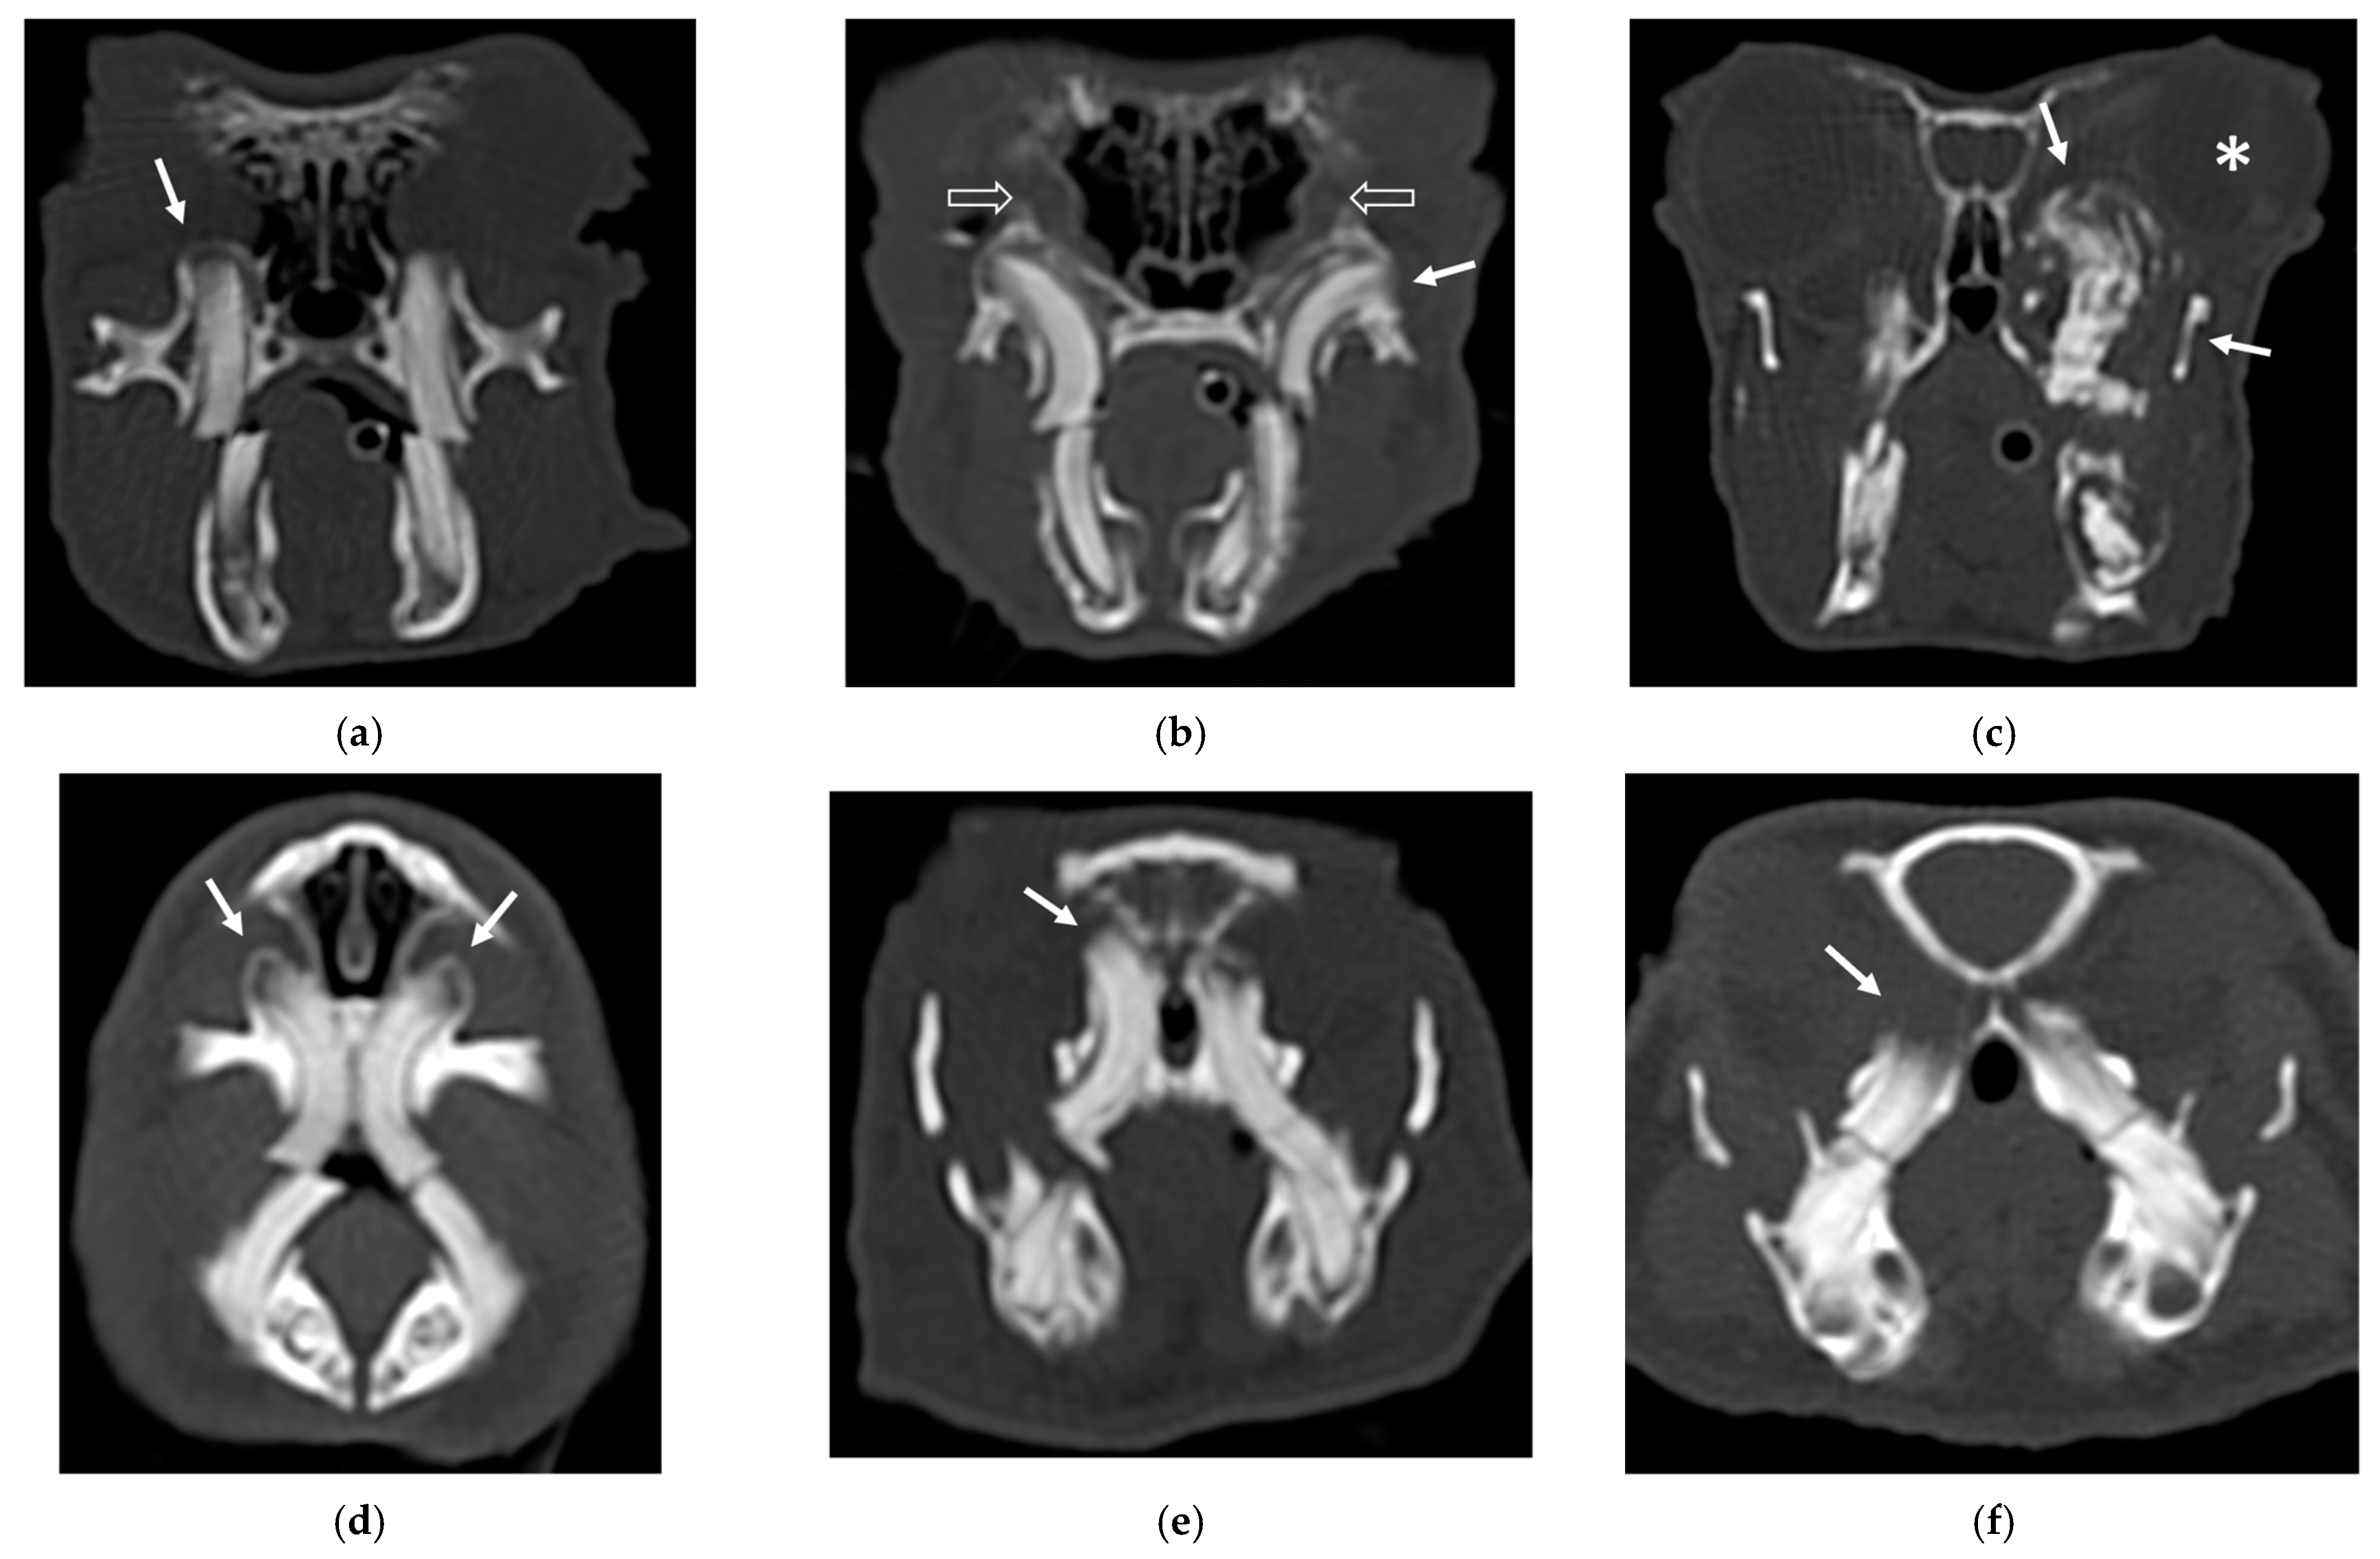

An example of the three categories of secondary bone lesions is shown for rabbits and guinea pigs in Figure 1.

Figure 1.

Transverse CT images of maxillary secondary bone lesions of three rabbits (a–c) and three guinea pigs (d–f) included in the study; bone algorithm. (a,d) Bulging around tooth without focal lysis (white arrow); (b,e) bulging around tooth with focal lysis (white arrow). Note the concomitant presence of nasolacrimalduct enlargement in image (b) (empty white arrows); (c,f) aggressive bone lesion associated with teeth (white arrow). Note the associated exophthalmos in the image (c) (white asterisk).

Incisor teeth were pathological in only two cases (one rabbit and one guinea pig) associated with bulging around the tooth root with focal lysis (2). The involvement of the premolar and molar teeth exhibited variable distribution in both species in secondary bone lesions categories 1 and 2.